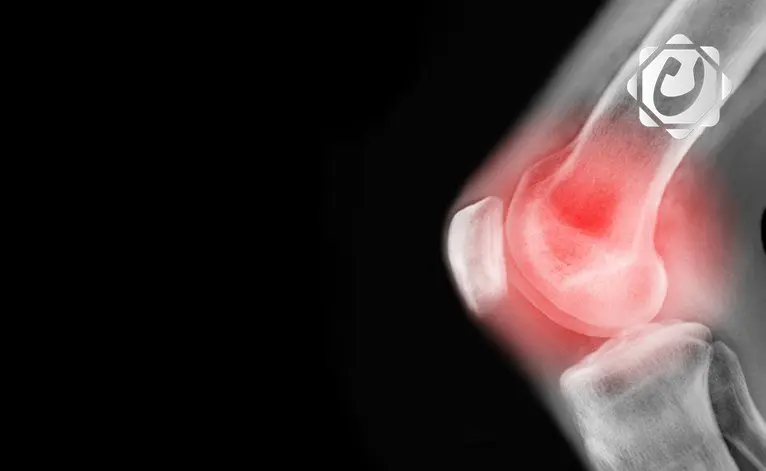

تعديل بسيط في أسلوب المشي يخفف آلام الركبة ويؤجل الجراحة لسنوات